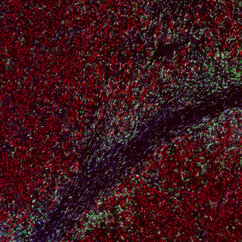

"The skin tumours we study develop resistance to targeted therapy in 75 to 80 percent of cases, which is quite alarming," says Lisa Haas, recent PhD graduate from the Obenauf Lab and first author of the study. "We found that acquired resistance to targeted therapy has a strong impact on the tumour’s immune cell composition, which could lead to resistance to immunotherapy."

The scientists found that tumours that had developed resistance to targeted therapy were short of a type of cells – dendritic cells – that are crucial to activate the immune system during immunotherapy. Not only were there fewer dendritic cells in these tumours, but they did not function properly. As a result, immunotherapy was ineffective in waking the immune system from slumber, and the tumours kept on growing, unnoticed.